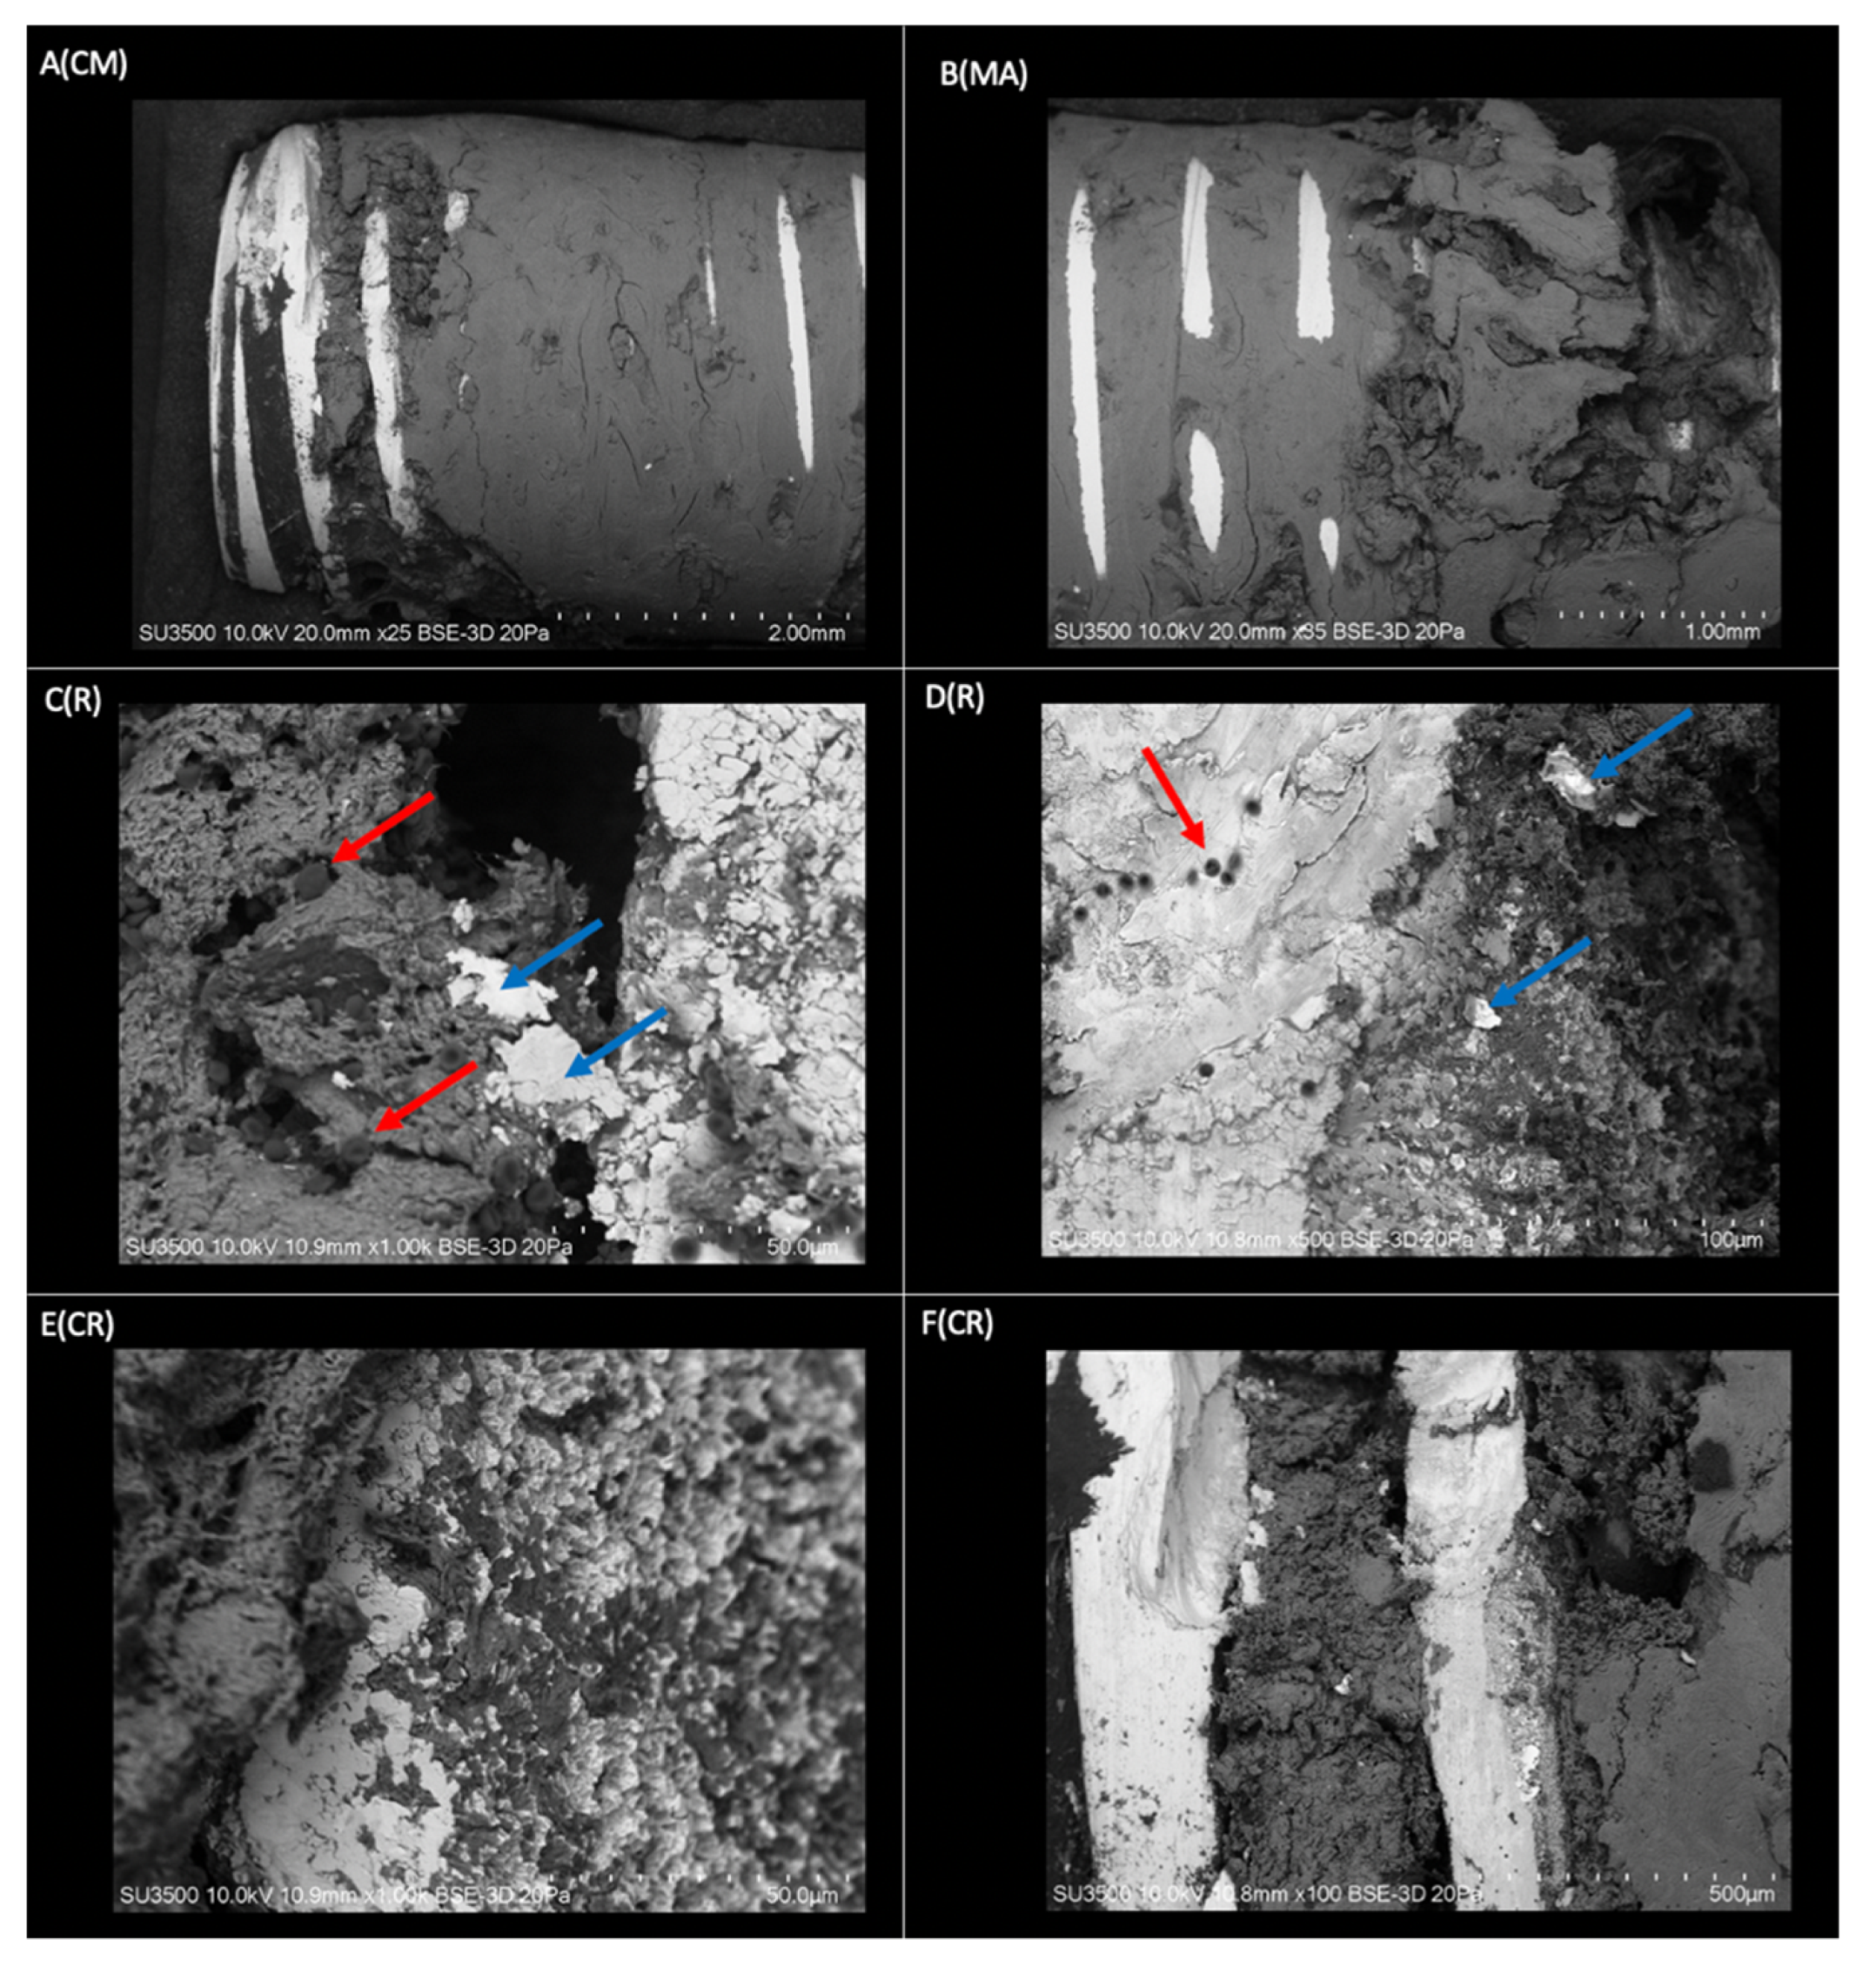

2.2. Surface Morphological Analysis of Osseointegrated Dental Implants

2.2.1. Morphological Analysis of the Dental Implant Surface

2.2.2. Superficial Morphological Analysis of Bone Tissue Associated with Dental Implants